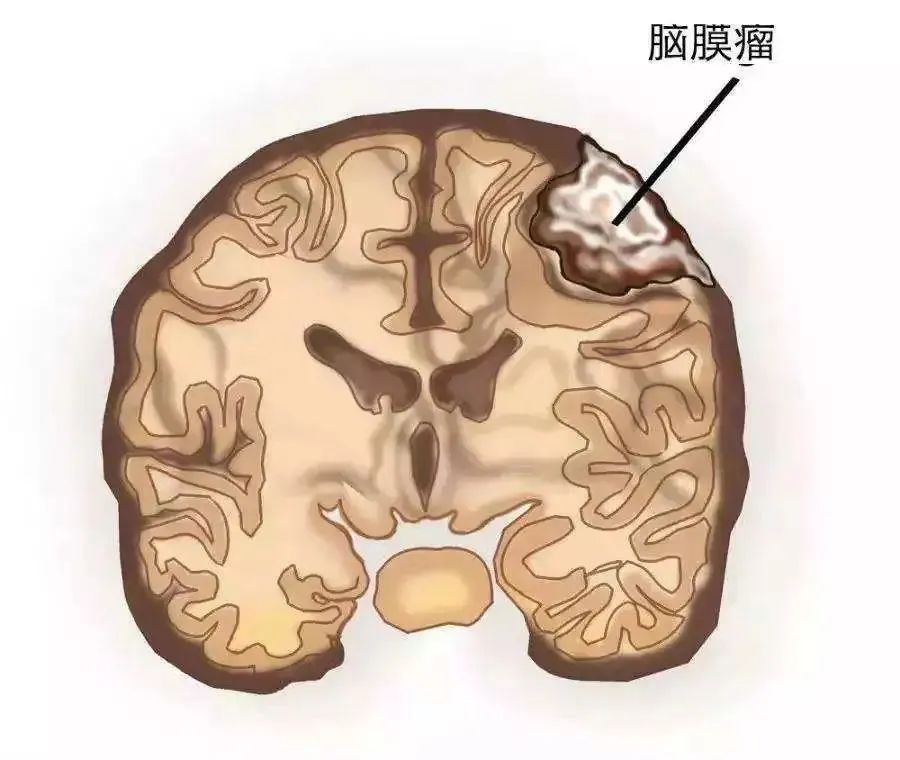

01 脑膜瘤

大约1/3的原发性脑肿瘤是脑膜瘤,通常为良性,生长缓慢。脑膜瘤从覆盖大脑和脊髓的组织中生长出来,并对这些区域造成压力。脑膜瘤在儿童中很罕见,在60岁以上的妇女中最常见。脑膜瘤的症状包括:头痛、手臂或腿力量虚弱、癫痫发作、人格改变和视力问题。